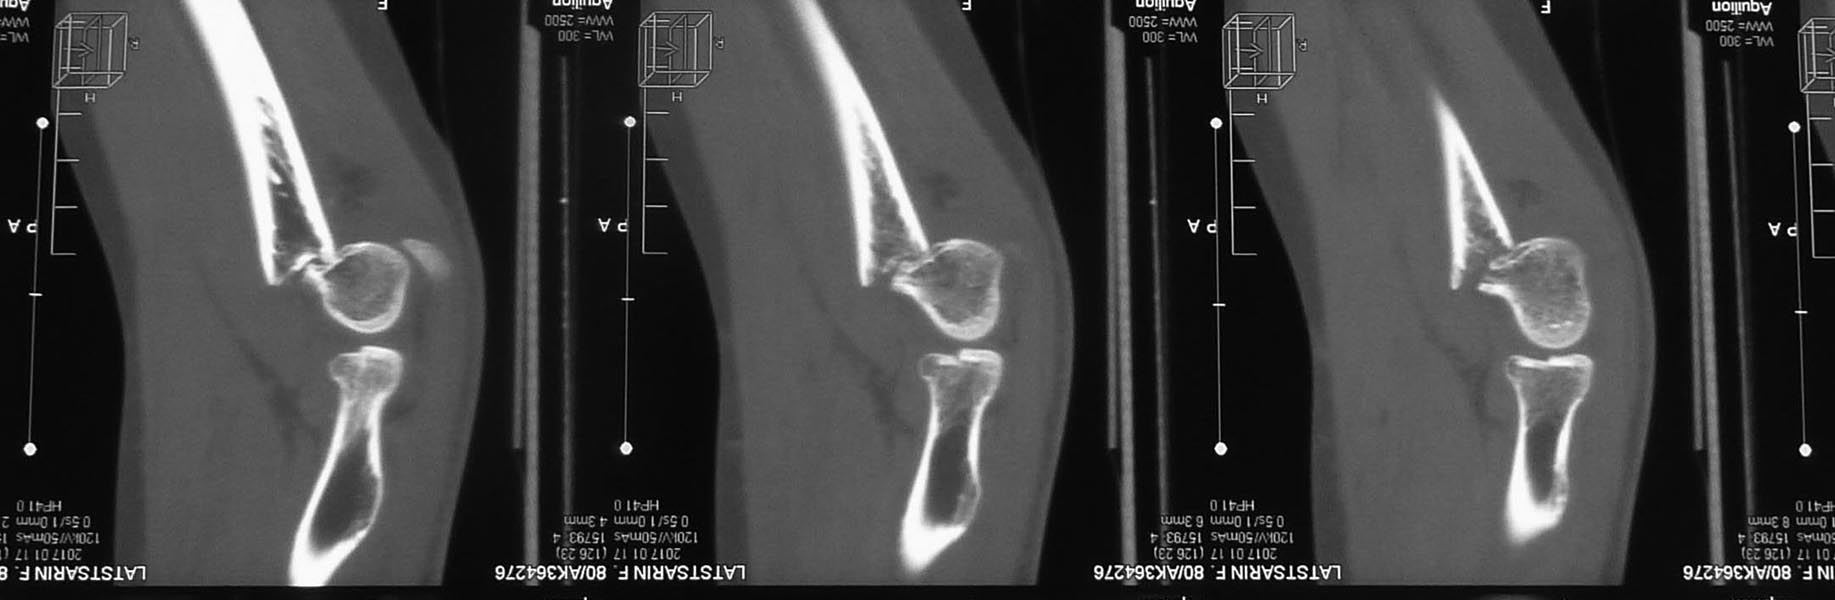

В данном случае имеется перелом головки лучевой кости 2 типа по Mason, который в изолированном варианте можно лечить консервативно. Сломанный фрагмент занимает менее 50% площади суставной поверхности головки лучевой кости и, судя по рентгенограммам, в положении супинации предплечья обращён кнаружи. Смысл делать остеосинтез есть только для предотвращения вторичного смещения при ранних движениях в локтевом суставе. В этом случае, на мой взгляд, такое смещение можно предотвратить, избегая сгибания в локтевом суставе при пронированном предплечье в течение 2 недель. Риск смещения при сгибании в локтевом суставе с предплечьем в супинации минимален.

Как обещал, выкладываю послеоперационные (на следующий день после операции) фото. Заранее прошу слишком проксимальную остеотомию локтевого отростка не ругать. Обычно делаю дистальнее.

А перелома головки луча на послеоперационных снимках даже не видно(возвращаясь к исходной теме)

Отличная работа! И выступание спиц оправдано! Предела лучшему нет: И проволоку можно провести непосредственно над периостом отростка во избежание диастаза и частичного прорезания проволоки через сухожилие. И концы спиц загнуть полукругом, для профилактики бурсита или перфорации кожи. И банальная первичная рентгенограмма в строго прямой проекции сустава могла избавить от серии КТ.

А как же ее делать у пациентки с таким переломом? Рентгенограмму в строго прямой проекции. Разогнуть локоть? И репозицию заодно сделать? Уж лучше КТ.